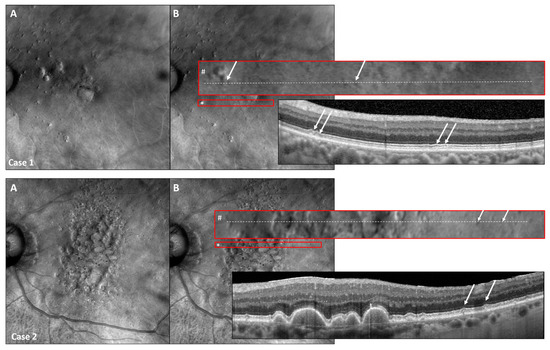

3.5. Retro Mode Detects Early Stages of SDDs